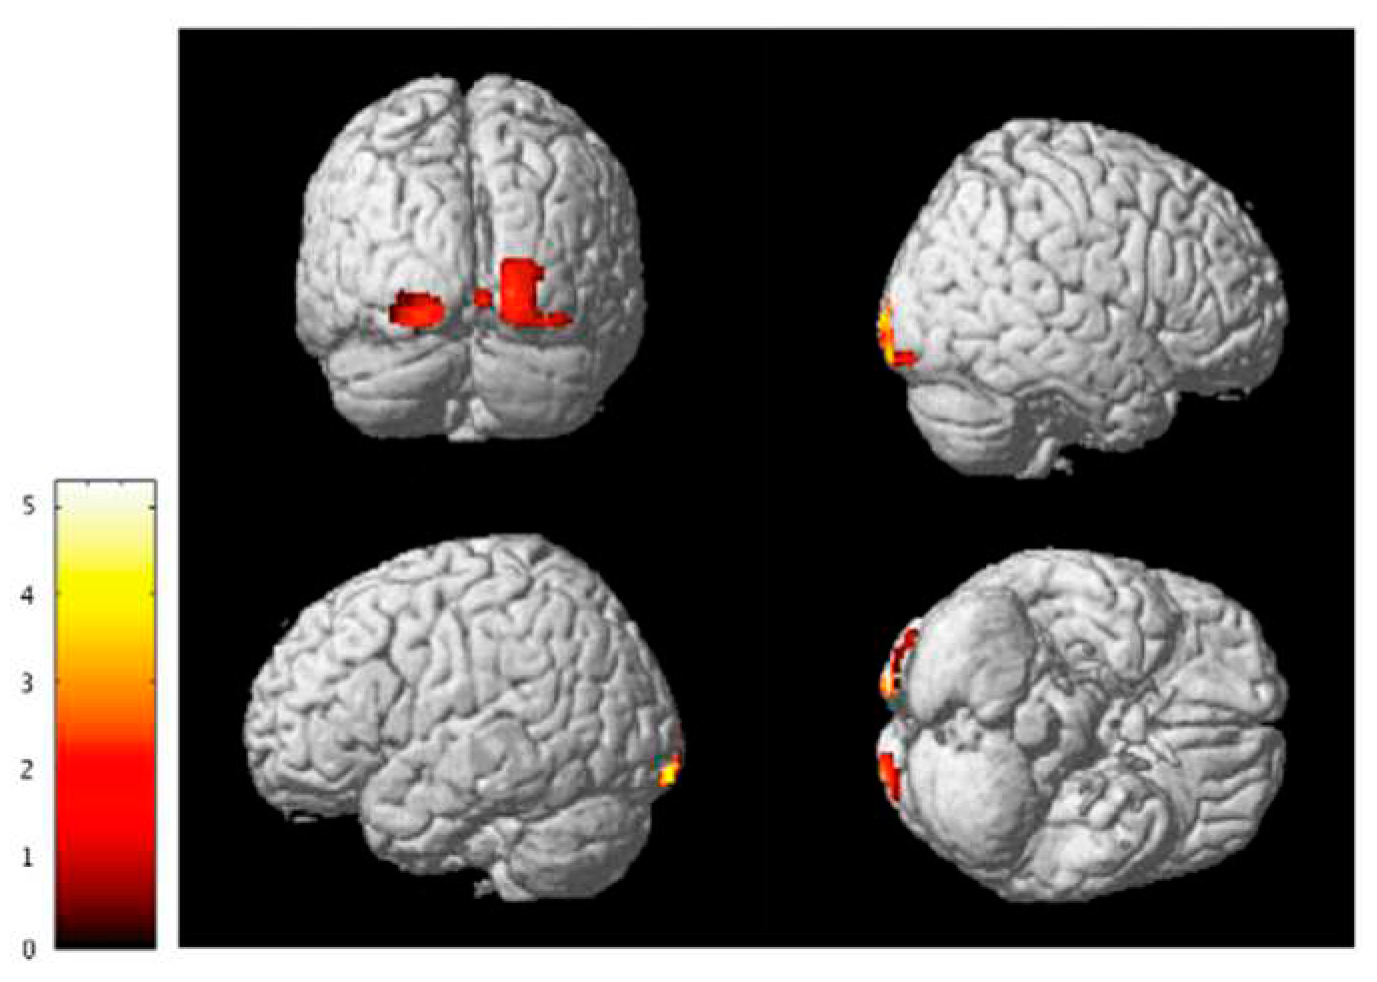

3.1. Voxel-Based Morphometry

- Huang, H.; Zheng, S.; Yang, Z.; Wu, Y.; Qiu, J.; Cheng, Y.; Lin, P.; Lin, Y.; Guan, J.; Mikulis, D.J.; et al. Voxel-based morphometry and a deep learning model for the diagnosis of early Alzheimer’s disease based on cerebral gray matter changes. Cereb. Cortex 2022, 33, 754–763. [Google Scholar] [CrossRef]

- Zhou, X.; Wu, R.; Zeng, Y.; Qi, Z.; Ferraro, S.; Xu, L.; Zheng, X.; Li, J.; Fu, M.; Yao, S.; et al. Choice of Voxel-based Morphometry processing pipeline drives variability in the location of neuroanatomical brain markers. Commun. Biol. 2022, 5, 1–12. [Google Scholar] [CrossRef]